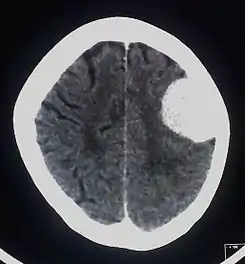

![]() TAC del cerebro con contraste radiológico donde se muestra un meningioma. | ||

Se requiere de una radiografía simple de cráneo, en la que se podrán observar con relativa frecuencia surcos vasculares aumentados de tamaño, signos de calcificación o hiperostosis o signos de hipertensión intracraneal crónica. En una TAC suelen aparecer lesiones muy bien delimitadas y usualmente se muestra una lesión hiperdensa tras administración de contraste que puede estar rodeado de edema y de base de implantación amplia. Es la modalidad que muestra de mejor manera las calcificaciones tumorales. Estas pueden ser nodulares, puntiformes o densas. La TC es muy efectiva para demostrar la hiperostosis (15-20%), osteolisis y erosión en el sitio de la inserción dural. También muestra el ensanchamiento de los surcos vasculares de la calota (arteria meníngea media). Se precisará en aquellos casos donde se necesite un mayor detalle óseo.